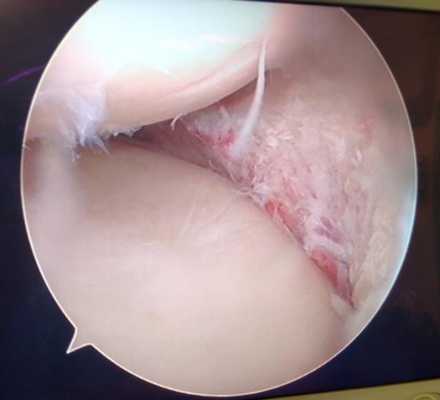

Продольные трещины на хряще большеберцовой кости после эпизода подкашивания после разрыва передней крестообразной связки коленного сустава.

Дегенеративные изменения суставного хряща коленного сустава появляющиеся на фоне повреждения разорванным мениском.